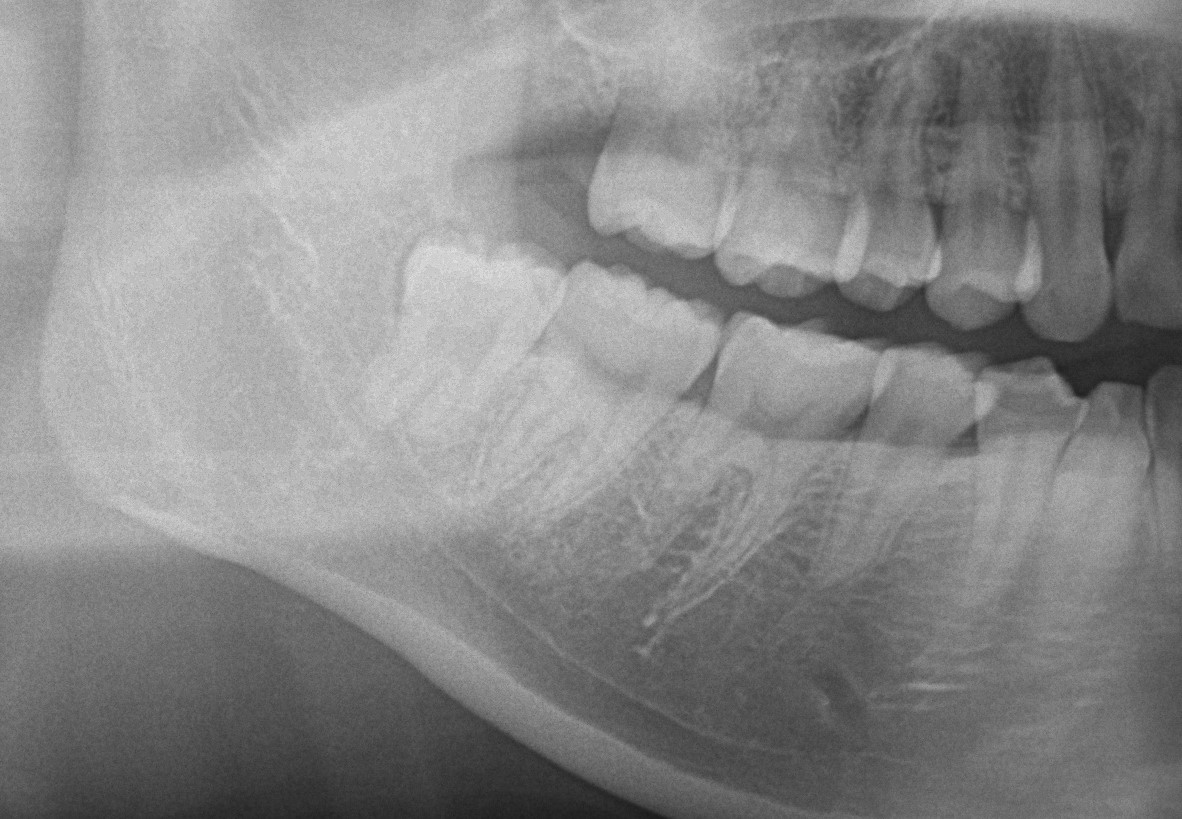

無切開抜歯について

今回は【無切開抜歯】と呼ばれる方法で抜歯した症例を1例動画で撮影したのでそれを報告していきます。 親知らずの抜歯は通常埋まっている歯なら切開→剥離→抜歯という手順を行っていきますが無駄に切開したり剥離すると術後の経過が悪 […]